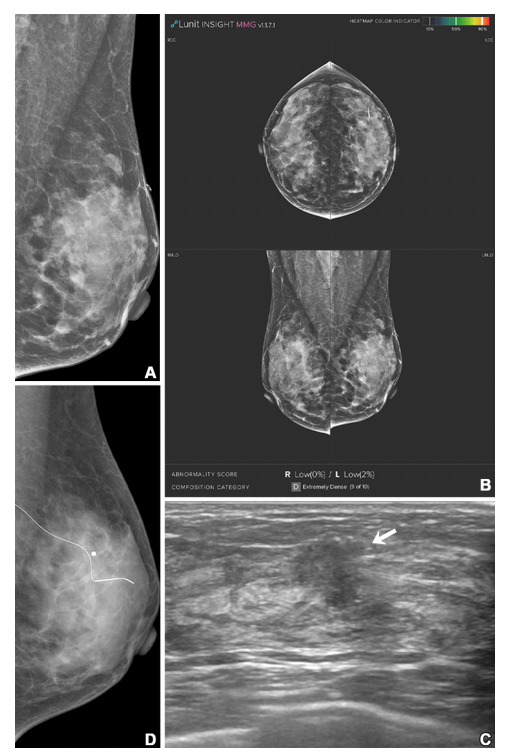

Figure 2: Imaging in a 51-year-old woman with extremely dense breasts (Breast Imaging Reporting and Data System category d). (A, B) Left mediolateral oblique digital mammogram (A) and right and left craniocaudal (RCC, LCC) and right and left mediolateral oblique (RMLO, LMLO) mammograms with artificial intelligence (Lunit INSIGHT MMG, version 1.1.7.1; Lunit) (B) show no abnormality. The radiopaque bar marker, which is attached on the skin to mark a previous benign fibroadenoma excision site, is visible. (C) Supplemental transverse US image shows a 1.2-cm irregular mass (arrow) in the left breast. (D) Left mediolateral oblique digital mammogram after US-guided wire localization shows no suspicious findings, even in retrospect. The radiopaque round marker, which is attached on the skin to mark the wire insertion site, is visible. The patient was treated with breast-conserving surgery, and the mass was proven to be invasive ductal carcinoma (pT1N0, 1.5 cm in size, estrogen receptor and progesterone receptor positive, human epidermal growth factor receptor 2 negative, histologic grade 1).

图2: 影像显示一名51岁乳腺极其致密的女性(乳腺影像报告与数据系统分类d)。(A, B) 左侧中斜位数字乳腺X线照片 (A) 和右侧及左侧头尾位 (RCC, LCC) 以及右侧及左侧中斜位 (RMLO, LMLO) 乳腺X线照片 (B) 使用人工智能(Lunit INSIGHT MMG,版本1.1.7.1;Lunit)辅助显示未见异常。附着在皮肤上的不透明标记条可见,用于标记之前良性纤维腺瘤切除手术的部位。(C) 补充横断面超声图像显示左乳房有一个1.2厘米的不规则肿块(箭头)。(D) 超声引导下的导丝定位后的左侧中斜位数字乳腺X线照片在回顾时仍未显示可疑发现。附着在皮肤上的不透明圆形标记可见,用于标记导丝插入部位。患者接受了乳腺保留手术,肿块被证实为浸润性导管癌(pT1N0,大小1.5厘米,雌激素受体和孕激素受体阳性,HER2阴性,组织学等级为1)。